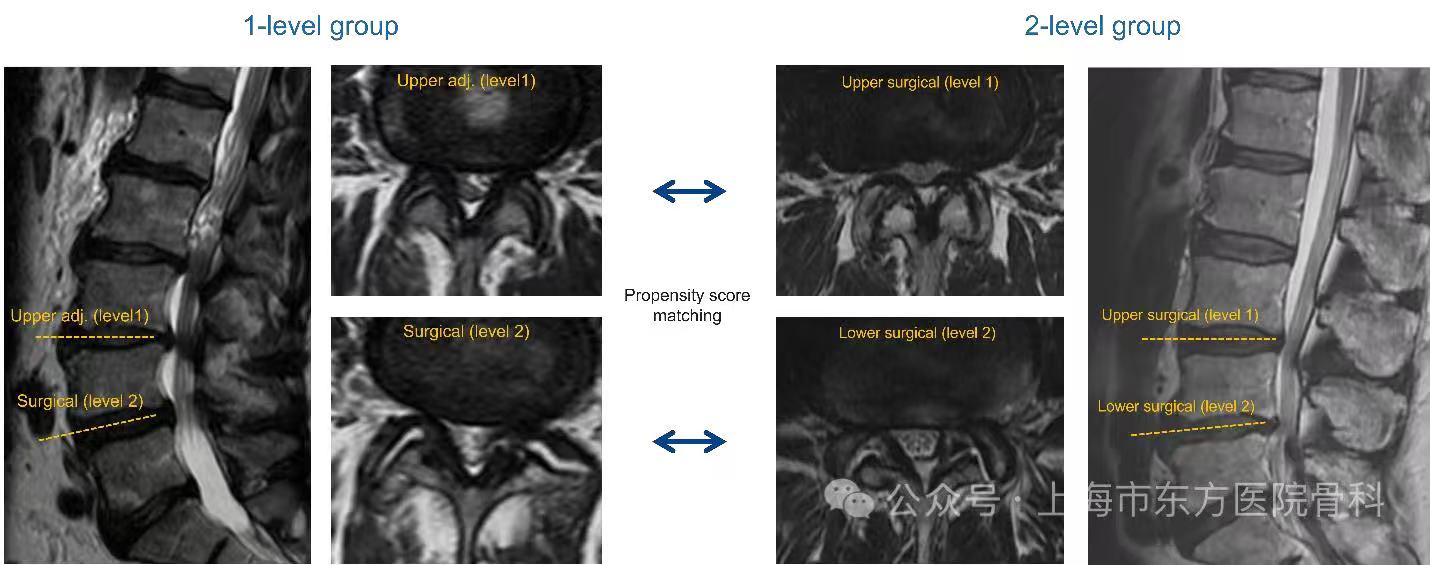

• 聚焦脊柱健康管理 “人工智能个性化脊柱健康测量平台”多中心临床研究正式启动